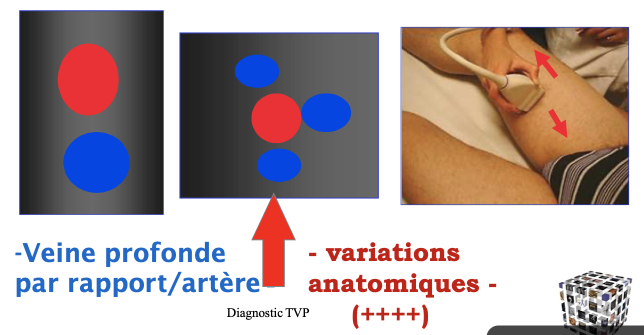

Veine fémorale profonde

Veine fémorale superficielle